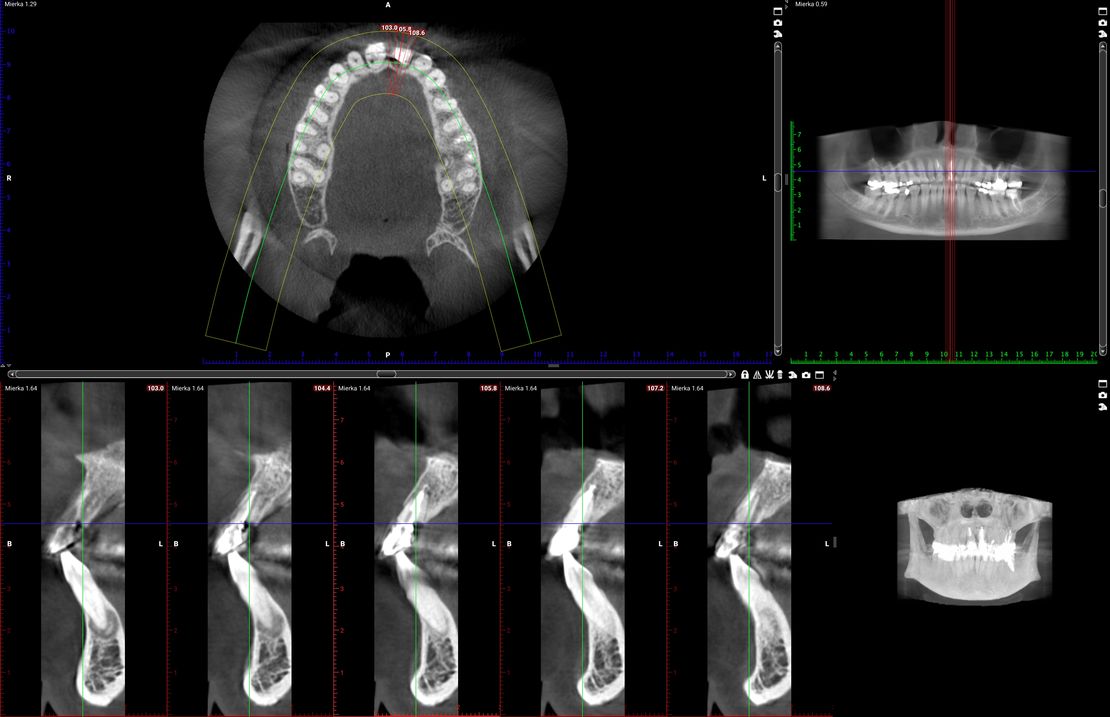

45-ročná pacientka sa obrátila na našu kliniku s bolesťou v oblasti horných stredných rezákov (obr. 1). Pri dôkladnom vyšetrení a CT diagnostike bola v oblasti zuba č. 11 zistená vertikálna fraktúra koreňa (obr. 2). V oblasti zuba č. 21 palatinálne bol prítomný hlboký kaz koreňa (obr. 3).

Jediným riešením bola extrakcia obidvoch zubov. Najväčšou obavou zo strany pacientky bola strata obidvoch predných zubov a následného fungovania bez nich pri práci s ľuďmi. Ideálnym riešením teda bola náhrada zubov implantátmi spolu s nasadením koruniek, a to počas jedného sedenia. V deň konzultácie bol pacientke urobený sken pomocou intraorálneho skeneru 3Shape TRIOS, ktorý nám umožňuje zobraziť 3D simuláciu ústnej dutiny. Pomocou softwaru 3Shape Implant Studio sme spojili dáta z intraorálneho skenu a CBCT, STL a DICOM súbory. V ďalšom kroku sme virtuálne vložili implantáty v správnej protetickej polohe, navrhli šablónu pre ich zavedenie, namodelovali individuálne abutmenty a korunky (obr. 4). Kompletné dáta sme exportovali pre frézovanie a 3D tlač. V laboratóriu sa pomocou 3D tlačiarne vytlačila chirurgická šablóna, ktorá nám slúži na presné zavedenie implantátov – použili sme implantačný systém Dentium Super Line. Následne boli vyfrézované zirkonové abutmenty a plastové dočasné korunky(obr. 5).